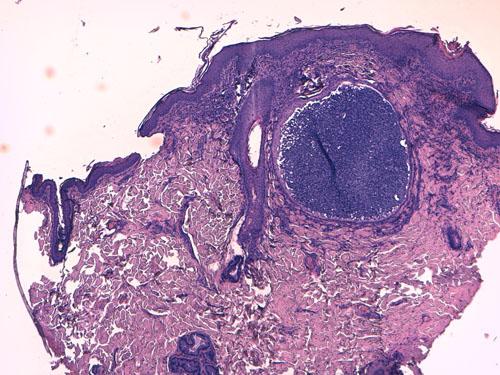

Une autre biopsie montre une folliculite luminale avec des polynucléaires neutrophiles altérés mais là-encore sans éléments figurés : il s’agit ici de lésions de pyodermite multifocale superficielle (Photo 8).

cas-de-toxidermie-chez-bichon8

Photo 8 : Foyer de pyodermite (folliculite luminale)